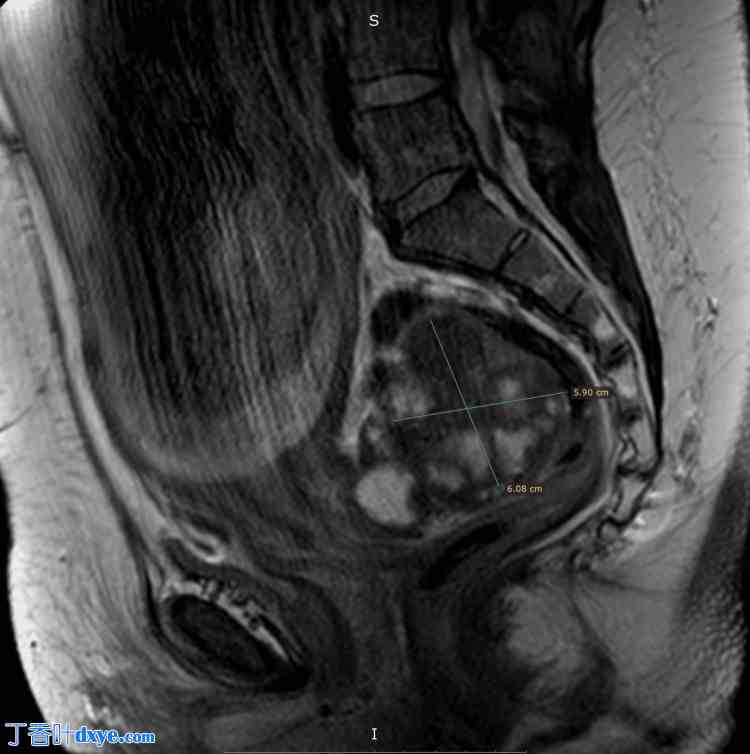

患者是一位49岁的女性,三年前曾接受腹腔镜下切除一个10厘米FIGO 4级(国际妇产科联合会4期)纤维瘤的手术。她来院门诊进行常规妊娠监测,超声检查显示盆腔内有一个6x6厘米的菜花状肿瘤。为了更好地观察肿瘤及其与周围结构的关系,患者在妊娠28周时接受了磁共振成像(MRI)检查(图1、图2)。

图1. 妊娠28周MRI检查结果:肿瘤大小及位置(矢状面)。

MRI,磁共振成像。